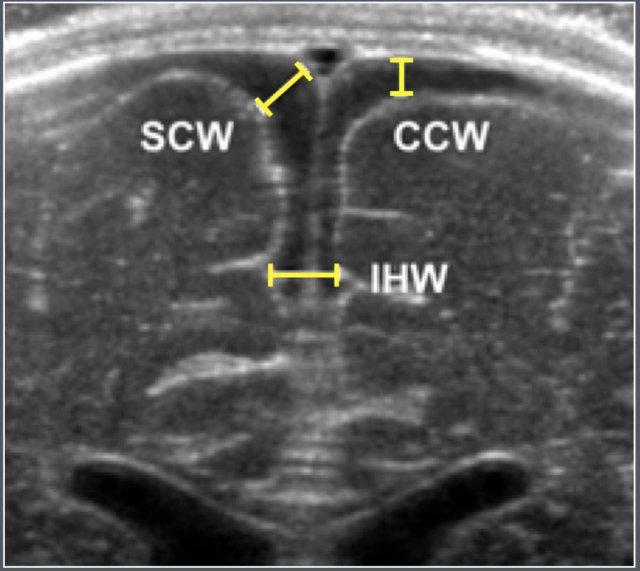

Các số đo được thực hiện trên mặt phẳng coronal tại mức lỗ Monro.

Các thông số siêu âm

- SCW: Chiều rộng xoang-vỏ não (Sinu-cortical width)

- CCW: Chiều rộng sọ-vỏ não (Cranio-cortical width)

- IHW: Chiều rộng liên bán cầu (Interhemispheric width)